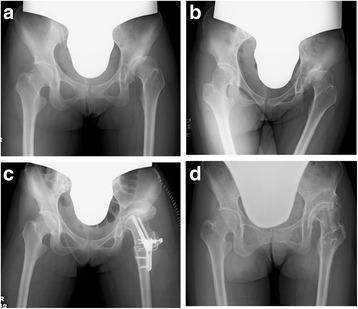

Figure 5a shows the radiographic image of a 24-year-old woman who presented to our department with a history of coxalgia on her right hip, which gradually deteriorated. The plane radiographic image of the hip showed AHD; however, the joint cartilage was preserved. Figure 5b shows the radiographic image immediately after RAO in which the coverage of the femoral head improved. Figure 5c shows the radiographic image 12 years after RAO; she did not have any symptoms on her left hip, and there was no joint space narrowing. Figure 6a shows the plane radiographic image of a 25-year-old woman with AHD and deformity of the femoral head. The joint space became wider when the hip was adducted, and the position of the loading area of the femoral head became horizontal (Fig. 6b); thus, we performed RAO with valgus femoral osteotomy (Fig. 6c). Figure 6d shows the radiographic image 10 years after the surgery; there was no progression of OA compared with the finding immediately after surgery. She had no pain or other complaints on her left hip.

Fig. 6.

Radiographic image of a 25-year-old woman treated with rotational acetabular osteotomy and valgus intertrochanteric osteotomy on her left hip. The preoperative radiographic image shows AHD with a deformity of the femoral head (a). The joint space becomes wider when the hip is adducted, and the position of the loading area of the femoral head becomes horizontal (b); thus, we performed RAO with valgus femoral osteotomy (c). There is no progression of OA 10 years after the surgery compared with the finding immediately after surgery, and she had no pain or any complaints on her left hip (d)